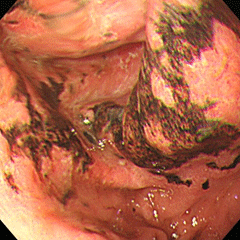

便秘を主訴に来院。S状結腸に全周性の進行がんを認めました。

上腹部痛を主訴に来院。横行結腸に全周性の進行がんを認めました。

下腹部痛・食欲不振を主訴に来院。S状結腸の便を洗い流すと、1/4周性の進行がんが明らかになりました。

すべて進行がんです。下段の2枚は同じ患者さんです。

横行結腸がん(大腸がん⑨)に対し手術が行なわれ、6ヶ月後の検査で下行結腸に新たに進行がん(大腸がん⑩)が認められました。